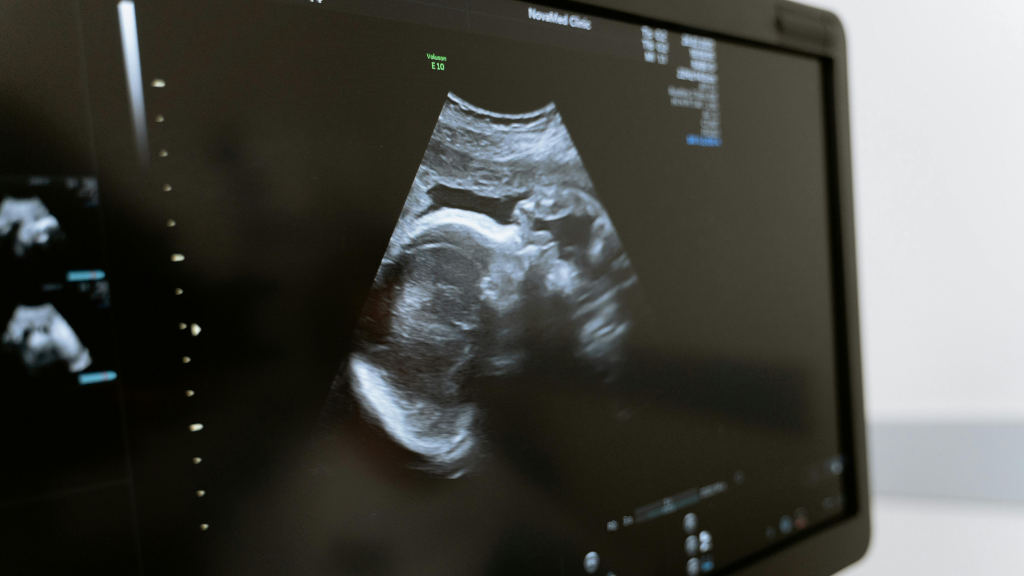

Siêu âm thai đã trở thành một phần không thể thiếu trong việc chăm sóc sức khỏe bà bầu. Nhờ công nghệ này, các bác sĩ có thể theo dõi sự phát triển của thai nhi một cách chi tiết và chính xác. Một trong những chỉ số quan trọng được đo lường trong siêu âm là OFD. Vậy OFD là gì và tại sao chỉ số này lại quan trọng? Trong bài viết này, chúng ta sẽ khám phá khái niệm OFD dùng trong siêu âm thai, cách thức đo lường và vai trò của nó trong việc đảm bảo một thai kỳ khỏe mạnh.

OFD, hay Occipitofrontal Diameter, là một trong những chỉ số quan trọng được đo lường trong quá trình siêu âm thai. Đây là khoảng cách từ trán đến chẩm của đầu thai nhi, được đo bằng cách sử dụng sóng siêu âm.

Trong siêu âm, OFD thường được đo cùng với các chỉ số khác như đường kính lưỡng đỉnh (BPD), chu vi vòng đầu (HC), chu vi vòng bụng (AC) và chiều dài xương đùi (FL) của thai nhi để đánh giá sự phát triển toàn diện của thai. Việc đo lường OFD giúp các bác sĩ và chuyên gia y tế có cái nhìn chi tiết về kích thước và hình dạng của đầu thai nhi.